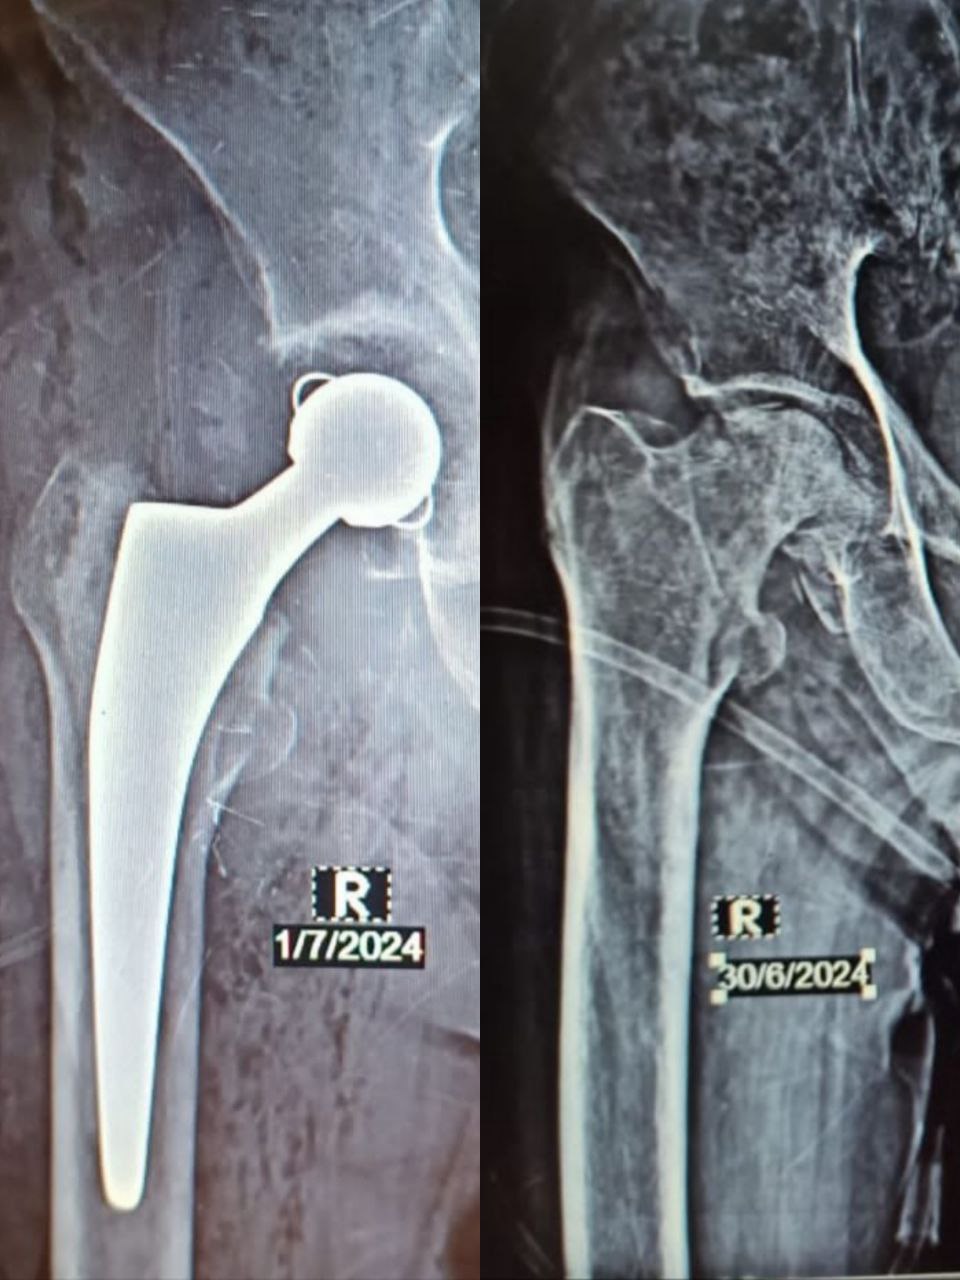

مفصل ورك لا أسمنتي

قبل وبعد تبديل مفصل ورك صناعي مع تطعيم عظمي للعمود الخلفي العلوي بطعم ذاتي من الرأس بتنفيذ دقيق بالتعاون بين شركتنا والدكتور [وليد العبد]. النتيجة: ثبات ممتاز ووضع تشريحي أنيق يعكس جودة العمل ودقة التقنية